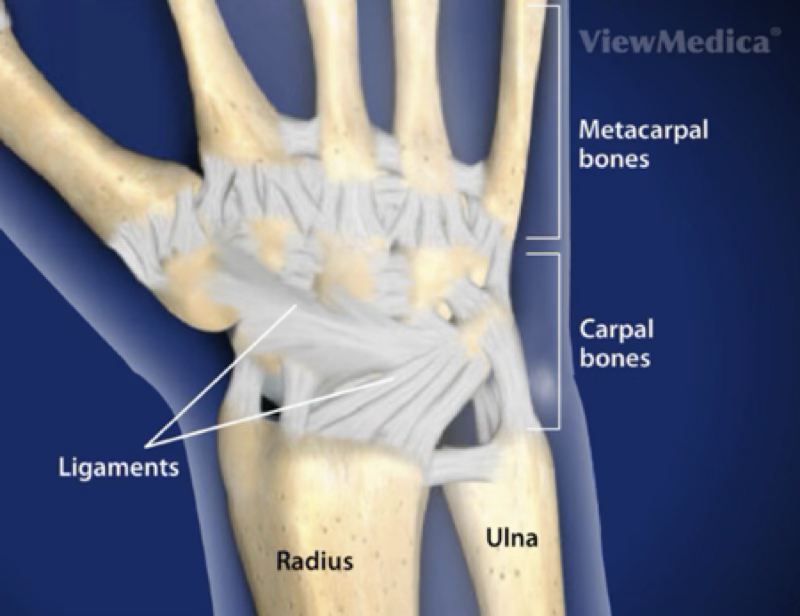

how many bones are in your hands?

8 carpals, 5 metacarpals, 2 sesamoids, 14 phalanges

wrist sprain

most common wrist injury

occurs with an abnormal, forced movement (falling on hypertext wrist or violent flexion)

symptoms: pain, swelling, tenderness, difficulties with ROM

treatment: can send for images to rule out a fracture

can splint if brace if bad enough

treatment for pain management (meds, modalities)

can prevent or treat with wrist tape